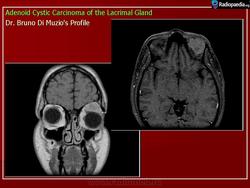

Диагноз устанавливают только после гистологического исследования. Предположительный диагноз может быть установлен на основании анализа клинических симптомов и результатов инструментального исследования. При рентгенографии на фоне увеличенной в размерах орбиты выявляются участки костной деструкции, чаще в верхненаружной, верхней и наружной стенках орбиты. Компьютерная томография позволяет определить протяженность тени опухоли, неравномерность ее краев, распространение в прилежащие экстраокулярные мышцы и неравномерность контуров костной стенки орбиты или ее полное разрушение, а ультразвуковое исследование — лишь наличие тени опухоли и ее плотность. Радиосцинтиграмма орбиты при аденокарциноме характеризуется увеличением коэффициента асимметрии, свойственного злокачественным опухолям. Информативна дистанционная термография, особенно с сахарной нагрузкой. Уточнить диагноз помогает дооперационная тонкоигольная аспирационная биопсия.